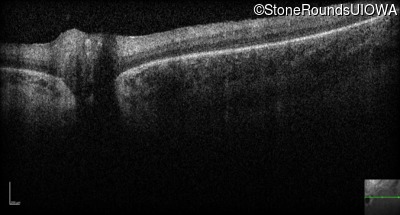

Optical Coherence Tomography - Right - Hand Motion sc

Exemplar / OCT Stack